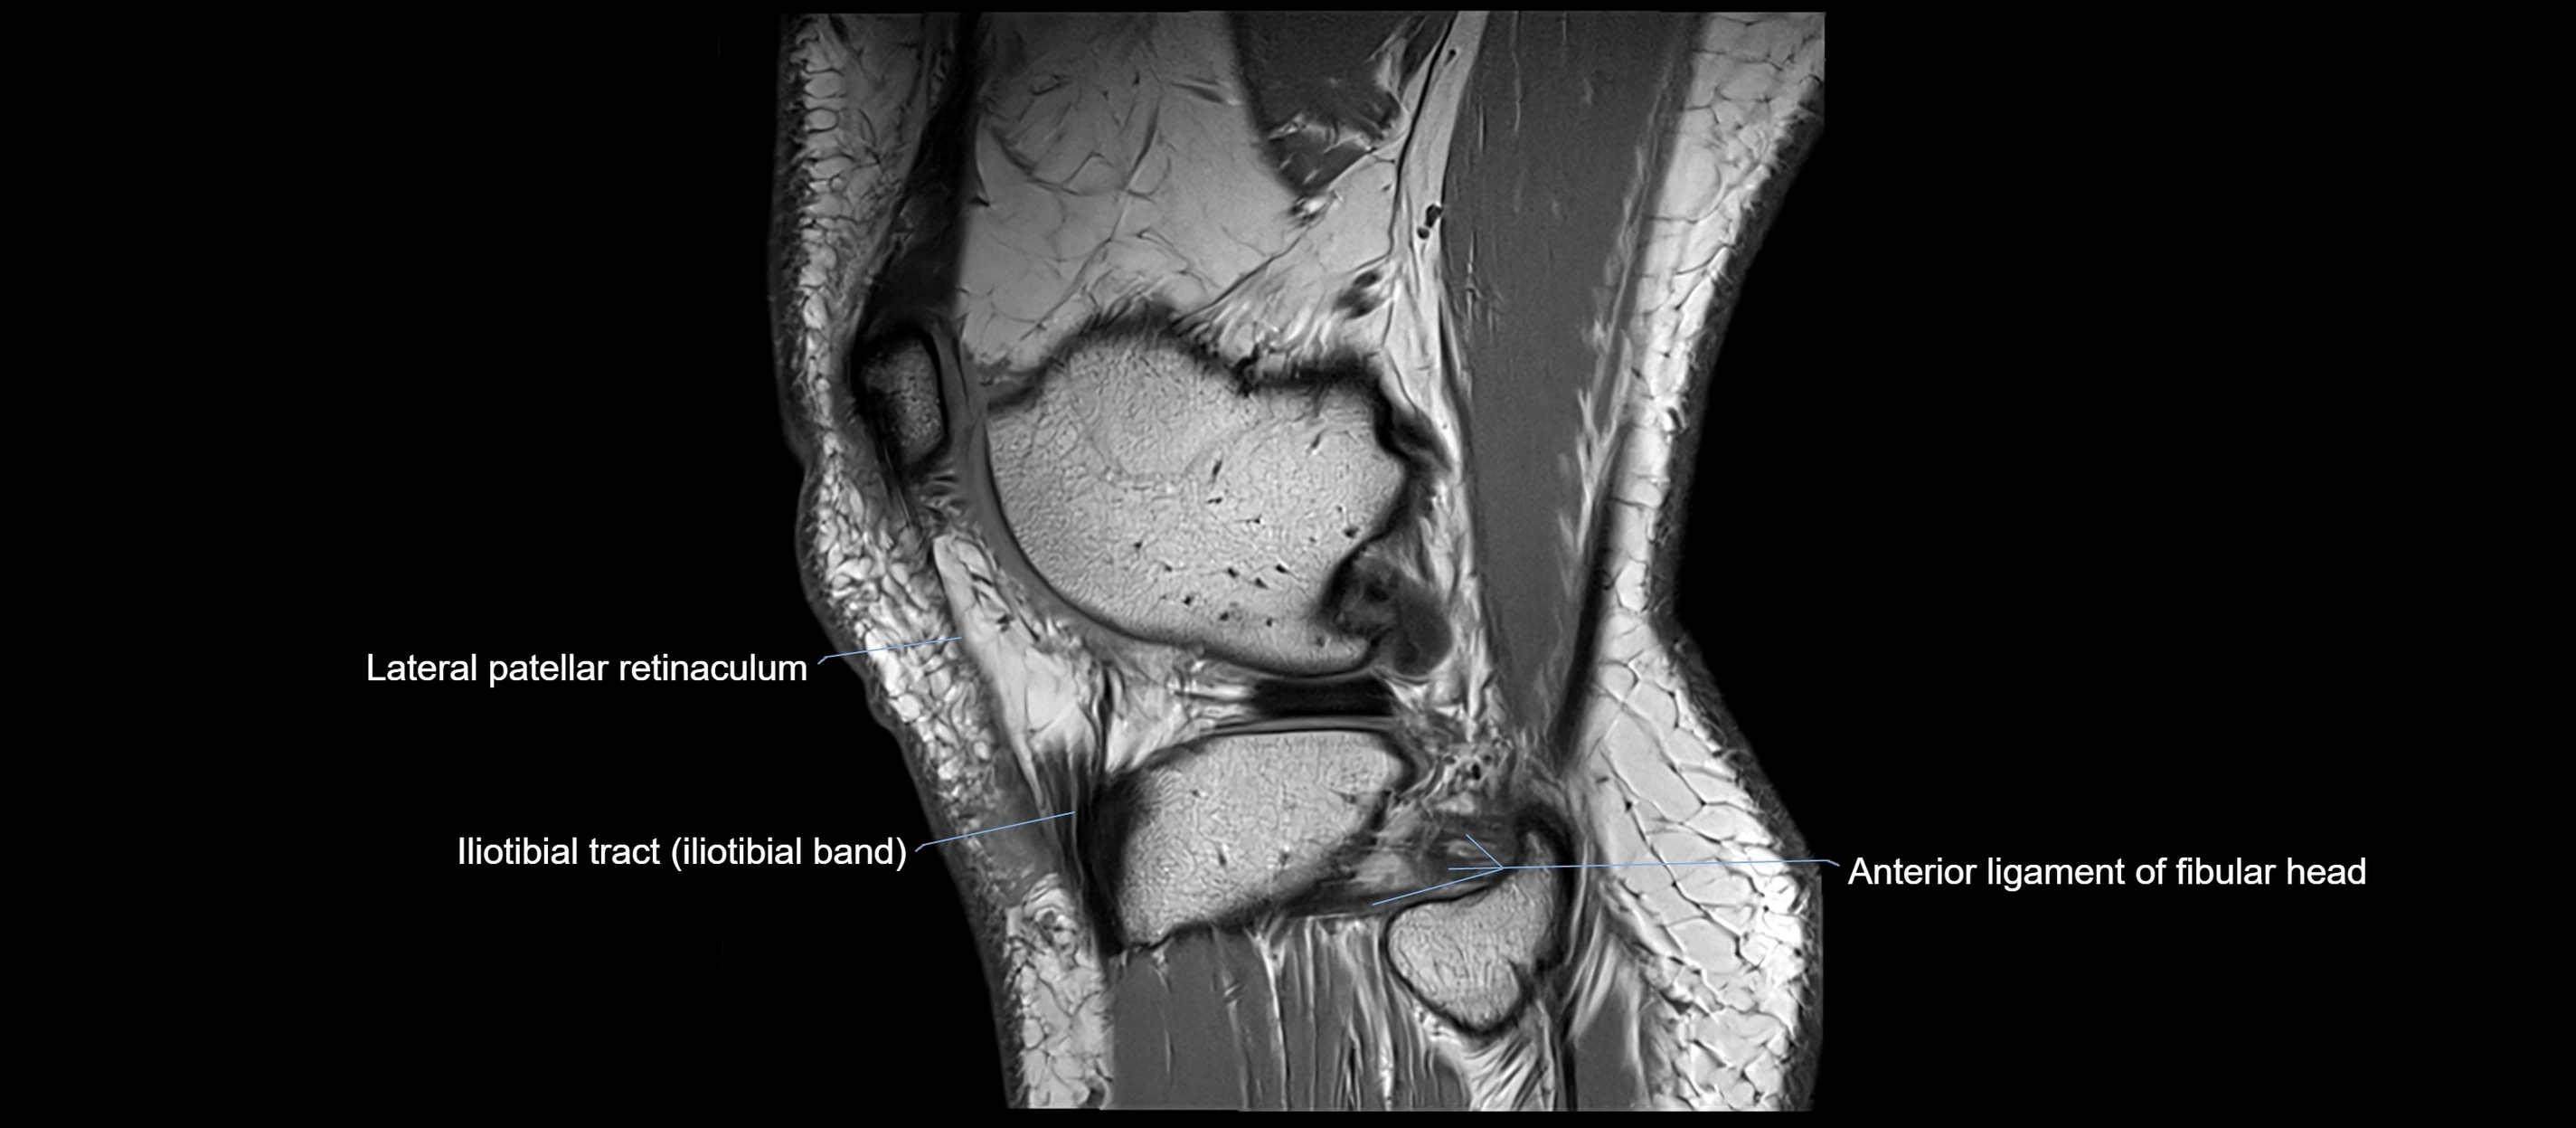

MRI images

image